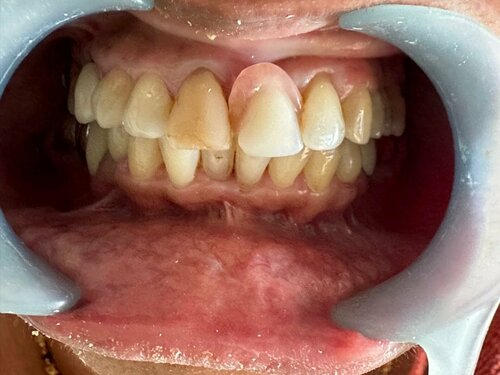

Dr. Gautami Phadke, Consultant Dental Surgeon and Root Canal Specialist in Karve Nagar, Pune, recently transformed a patient’s smile by addressi...